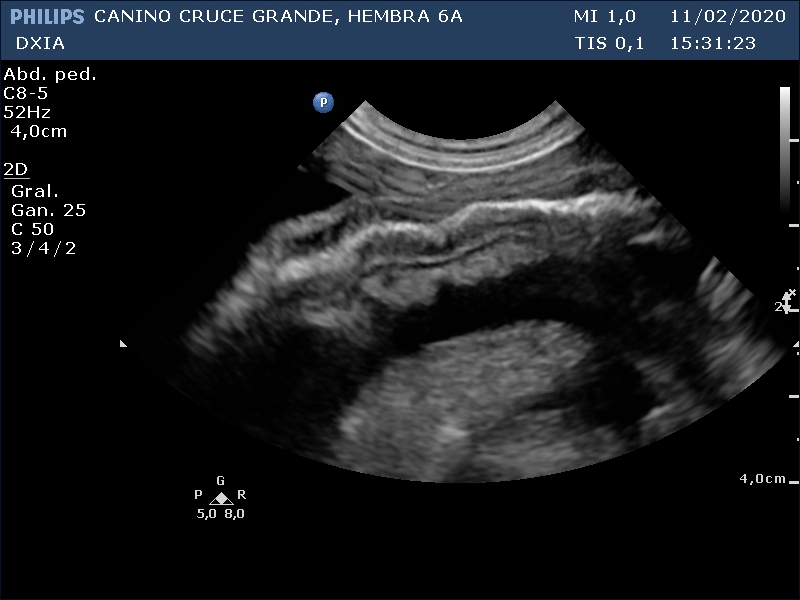

Se incluyen 3 imágenes del estudio:

Asas intestinales flotando en líquido libre abdominal